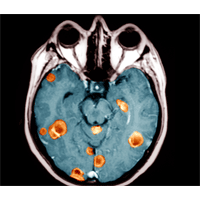

متخصصان سرطان به‌تازگی موفق به کشف اسرار ژنتیکی سرطان مغز شده‌اند.

به‌گزارش خبرگزاری دانشجویان ایران (ایسنا) به‌نقل از مجله‌ی «ساینس» (Science)، ‌این متخصصان - که تک‌تک ژن‌ها را در تومورهای دو نوع از صعب‌العلاج‌ترین انواع سرطان‌های مغزی ردیابی و مطالعه کردند - دریافته‌اند که سرطان مغز بسیار پیچیده‌تر از آن است که تصور می‌شود و هم چنین پی‌برده‌اند که چرا پس از رشد تومور احتمال درمان آن تقریباً وجود ندارد.

اما درعین حال این پژوهشگران یک روش جدید بالقوه برای درمان یک نوع شایع و کشنده‌ی سرطان مغز را کشف کرده و با این دستاورد راه را به‌سوی تشخیص سرطان پیش از گسترش آن در بدن هموار کردند.